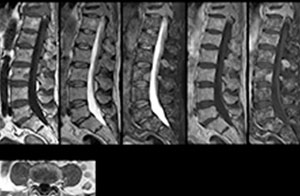

Examen de routine du rachis cervical

Ce patient s’est présenté avec des maux de tête aggravés par la flexion du cou, et on constate une malformation de Chiari de type I avec des amygdales cérébelleuses basses ainsi qu’un changement thrombolytique cervical dégénératif.